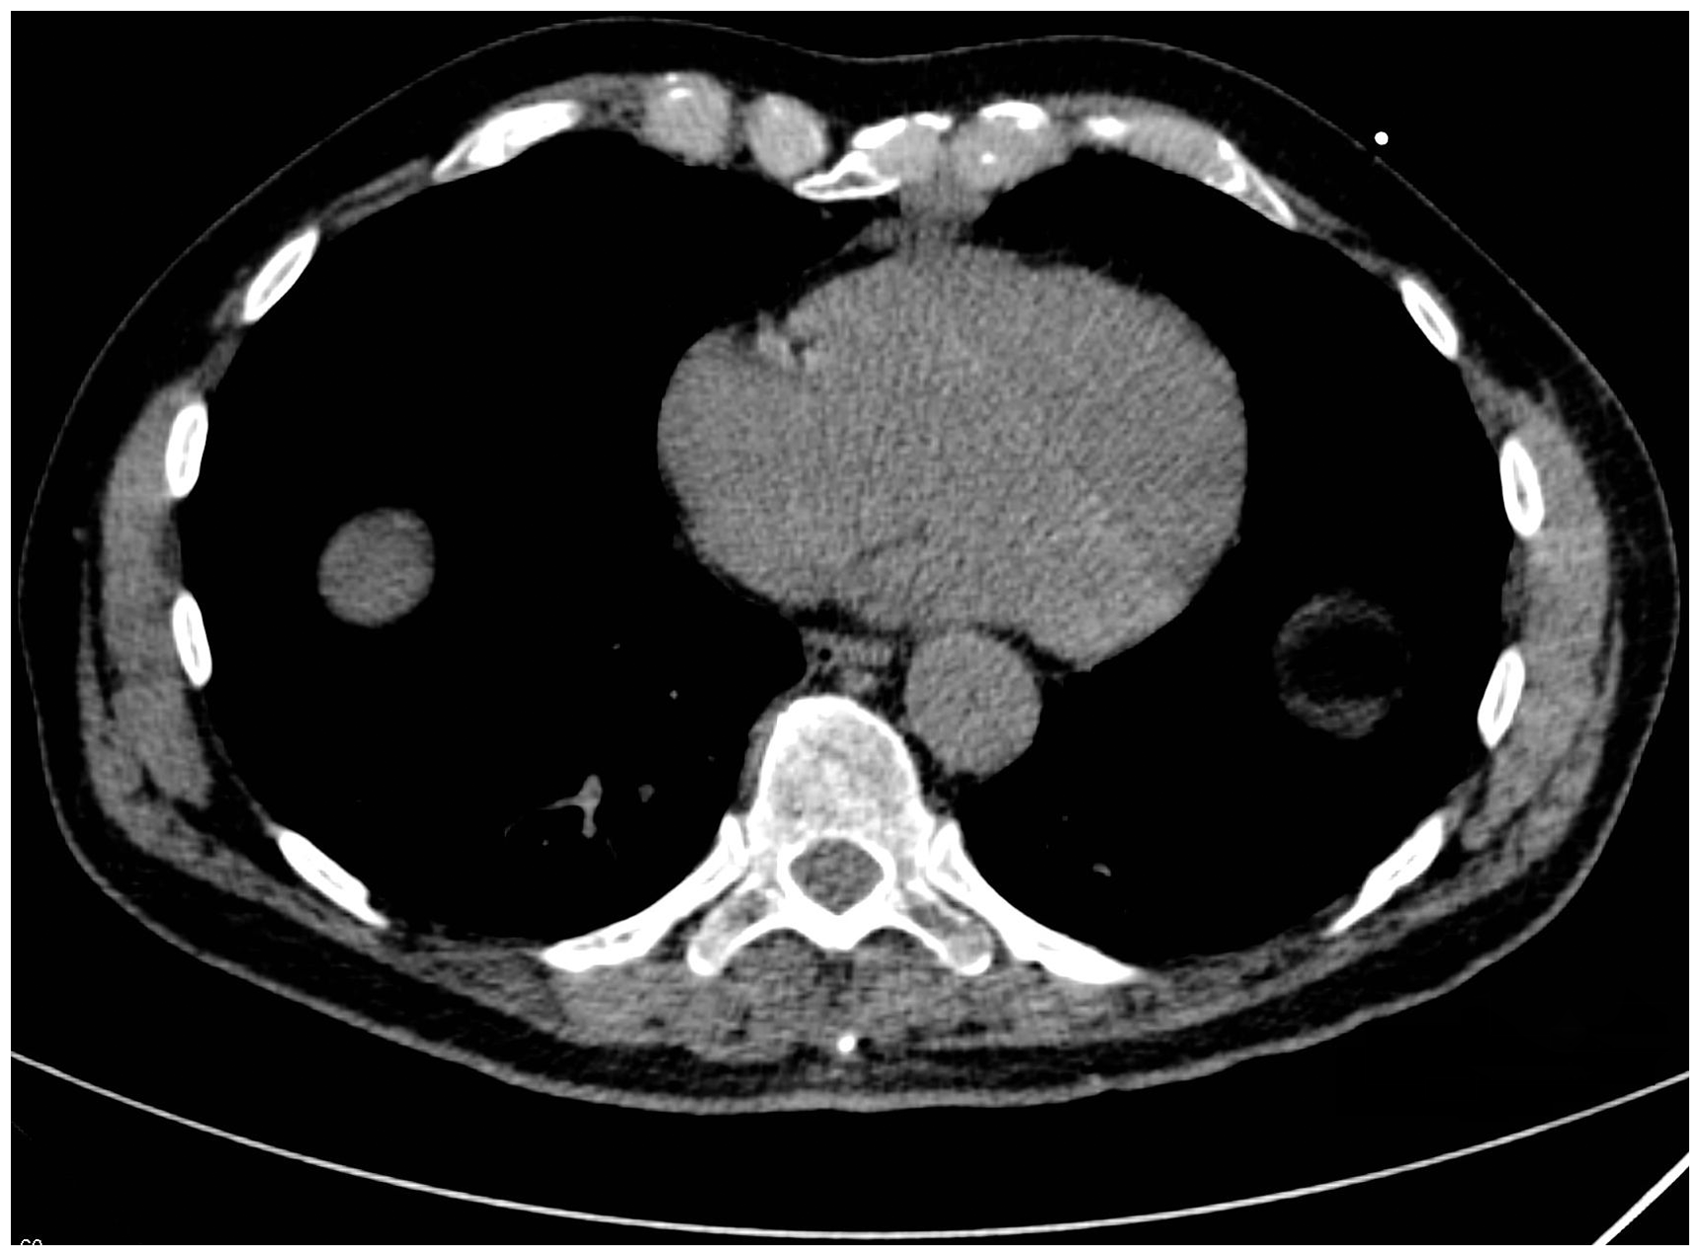

CT revealed a 4.3 × 2.6 × 3.3 cm, round, well-defined tumor with smooth borders in the anterior mediastinum with close relation to the ribs (Fig. 1). A low dose CT scan had been performed 4 years earlier, where the tumor had been overlooked (Fig. 2). Since then it had doubled its size. Positron emission tomography (PET-)CT was performed and showed a mean standardized uptake value of 1.57 with a maximum of 1.89 in the tumor indicating a low risk of malignancy. A thymoma was considered as diagnosis (Fig. 3). A neurophysiological examination was performed due to suspicion of myasthenia gravis, but did not reveal any abnormalities. No laboratory findings could support the suspicion of myasthenia. The tumor was not accessible for CT-guided biopsy and it could not be diagnosed on ultrasound due to poor visualization. Despite the lack of positive laboratory findings for myasthenia, the patient was referred under the diagnosis of myasthenia gravis for surgical removal of the suspected thymoma.

Second CT scan of the chondrosarcoma. Tumor makes a slight compression of the heart. CT scan of the chondrosarcoma performed 4 years prior to diagnosis. Tumor is visible anterior to the heart, but unfortunately overlooked. PET-CT scan showing a slight FDG uptake in the tumor with a minor compression of the heart.

We have described a rare case of a chondrosarcoma originating from the cartilaginous part of the ribs, which has only been reported twice previously. The tumor in the reported case was strongly suspected to originate from the cartilaginous part of the ribs due to the localization on the CT scan where it was not in connection with the sternum. A search in PubMed revealed eight cases of chondrosarcoma in the anterior mediastinum: two cases originating from the sternum (4,5); one believed to arise from cartilage (6); one from the thyroid cartilage (7); and four without relation to ribs or sternum (8–11). All tumors were described as heterogeneous masses on CT without cystic components, but with calcifications. Five of the cases had initial symptoms of chest pain while two had impaired breathing. In our case the tumor was homogeneous, without calcifications and with low Hounsfield values (HU 17) indicating fluid/cysts. It is possible that the chest pain that led to the first CT scan was caused by the chondrosarcoma.

Most often tumors of the anterior mediastinum are metastases from lung, breast, thyroid, or renal cancers. The incidence of chondrosarcomas is only 0.5 in 1 million but it is the most common primary tumor of the thoracic wall (12). Small thymomas are often well-defined, non-infiltrating, and soft tumors without calcifications. Usually they respect their surroundings and are clearly separated from these by fat, but 30–40% are invasive (13). In this case the tumor’s close relation to cartilage, the missing fat, the irregular form, and the compression on the heart could indicate that the tumor was not a thymoma. Other differential diagnoses could have been pericardial cyst, teratoma/dermoid cyst, unicentric debut of Castleman disease, or a cystic thymoma.